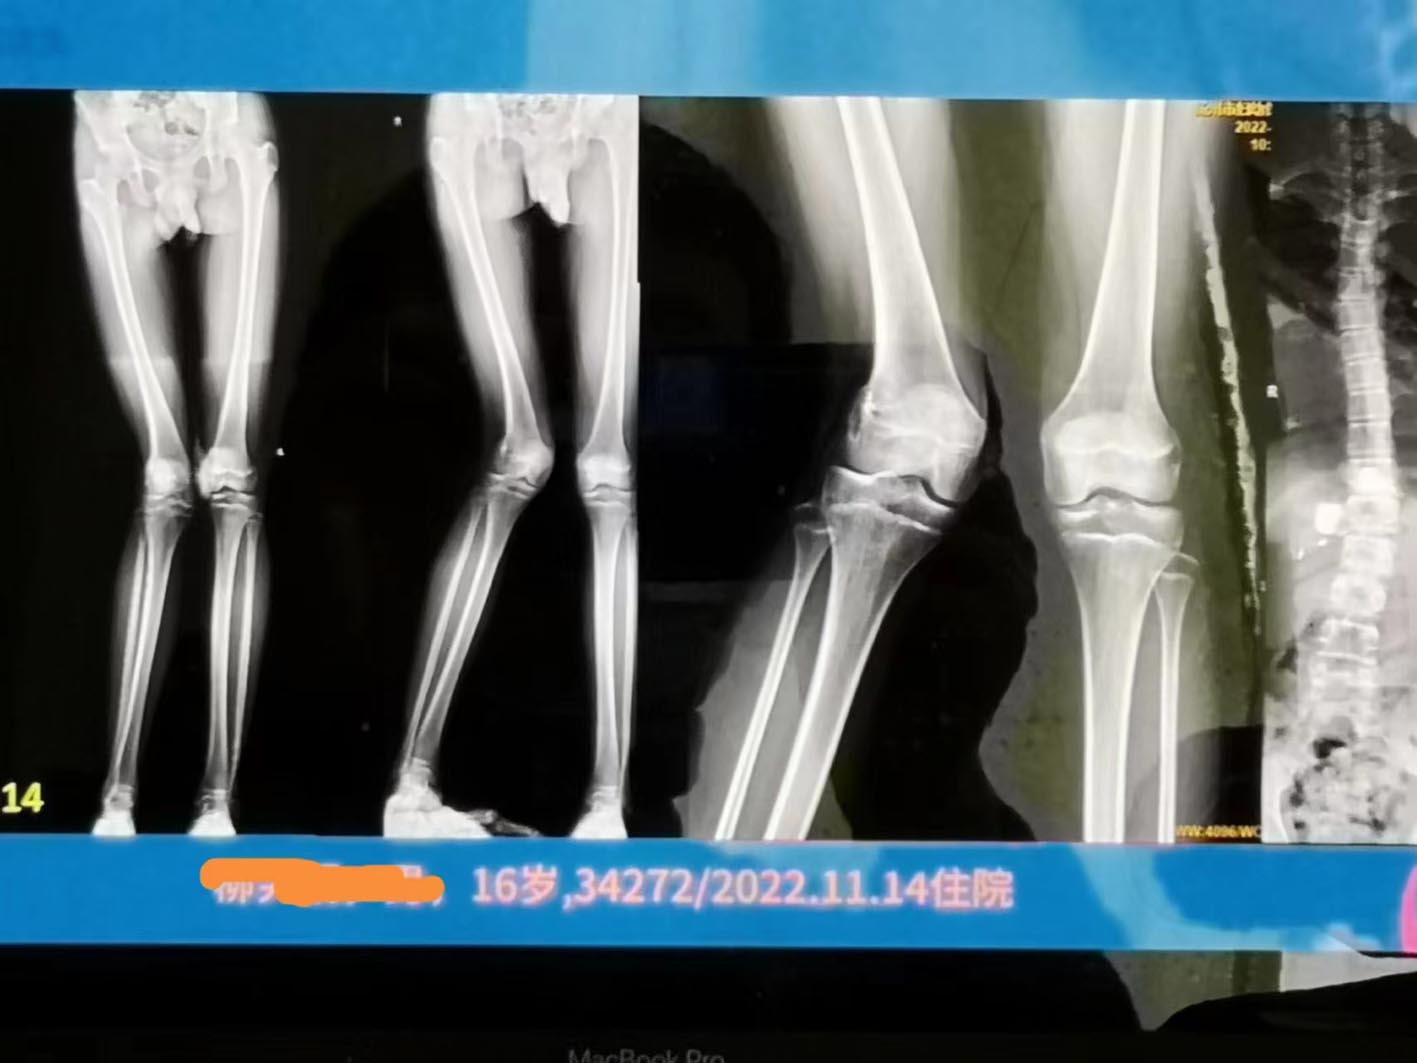

成功为一名16岁男孩矫正右腿k型和短缩畸形

图片尺寸1417x1063